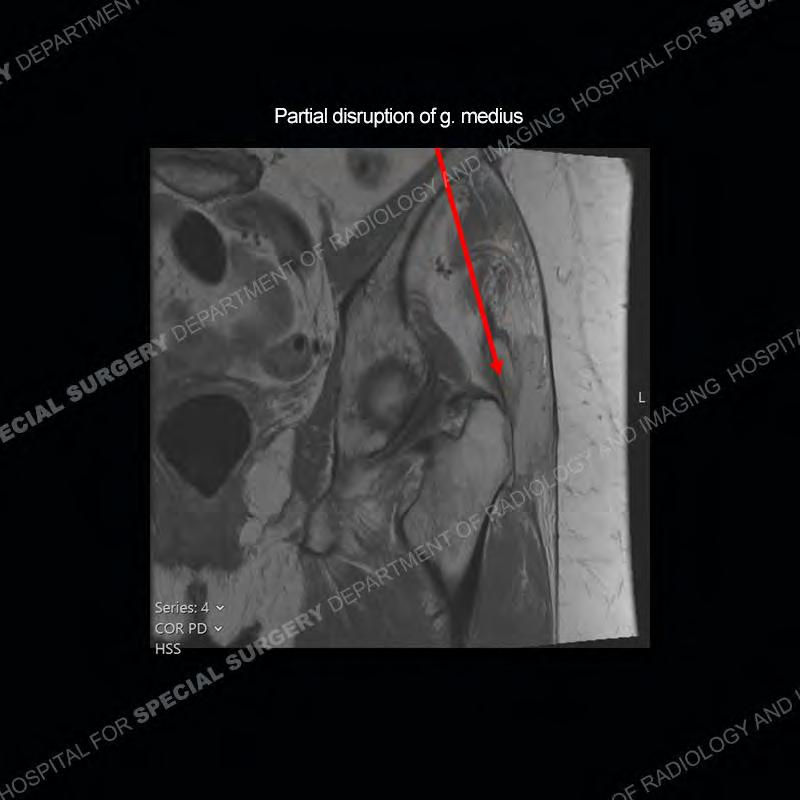

The radiograph is not particularly contributory in this case. The MRI demonstrates markedly abnormal architecture of the gluteus minimus and anterolateral band of the gluteus medius. Portions of the tendons are high signal, portions are highly attenuated, and portions are disrupted. A large, complex fluid collection is present in the adjacent soft tissue.

Diagnosis: Gluteal Tendinosis and Disruption with Complex Trochanteric Bursal Collection

Not as much of a diagnostic dilemma as many of the other cases shown but just a nice example of the pathology seen of the gluteal tendons and a cause of trochanteric pain. Although, frequently thought of in isolation, trochanteric bursitis or bursal thickening is much more commonly a reactive change to underlying pathology of the subjacent gluteal tendons. The gluteus medius is divided into a posterior band and an anterolateral band. Tendinosis and partial tearing very commonly will involve the gluteus minimus and especially the more posterior fibers and then propagate into the anterior lateral band of the gluteus medius. Involvement of the posterior band of the medius is much less common and engenders a marked degree of functional impairment.

The bursae about the greater trochanter can be a little bit confusing especially given the terminology. Trochanteric bursitis is implied to mean the subgluteus maximus bursa which is present deep to the maximus and just lateral/superficial to the trochanter. That is the bursa involved in this case. In this case the complexity of the bursa relates to the tendon tearing with inflammatory change and probably hemorrhage accounting for the complexity. Two other, less frequently involved bursa are also present. The subgluteus medius and subgluteus minimus bursa are found just deep to the named tendons. Although pathology does frequently follow the previously described pattern it is possible to have isolated pathology to either the medius or minimus.